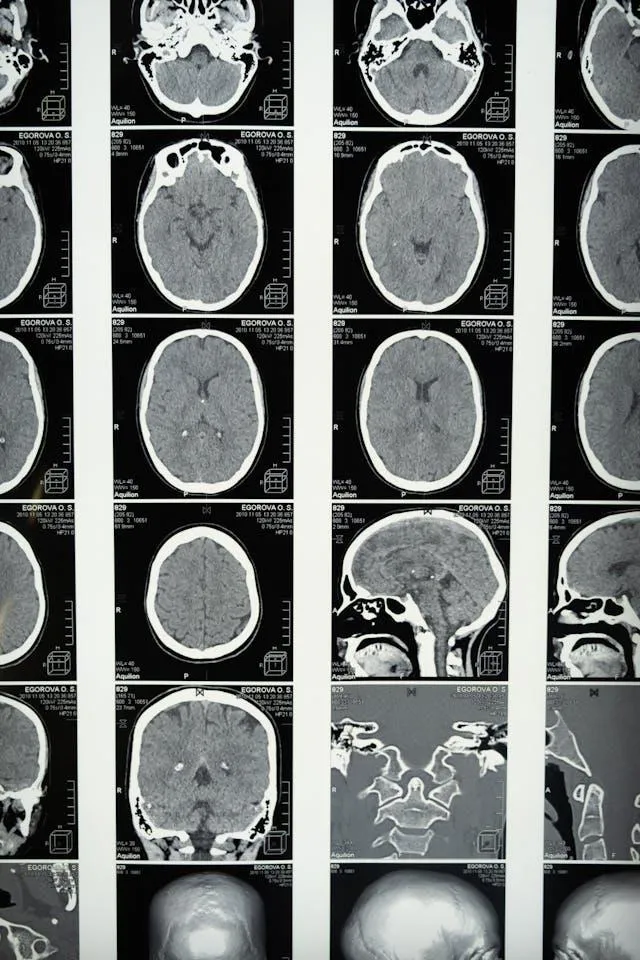

At its core, epilepsy is a chronic condition characterised by recurrent seizures caused by abnormal electrical discharges in the brain. These seizures can range from subtle moments of blank staring to dramatic convulsions. Importantly, one isolated seizure does not equate to epilepsy; it’s defined by two or more unprovoked seizures.